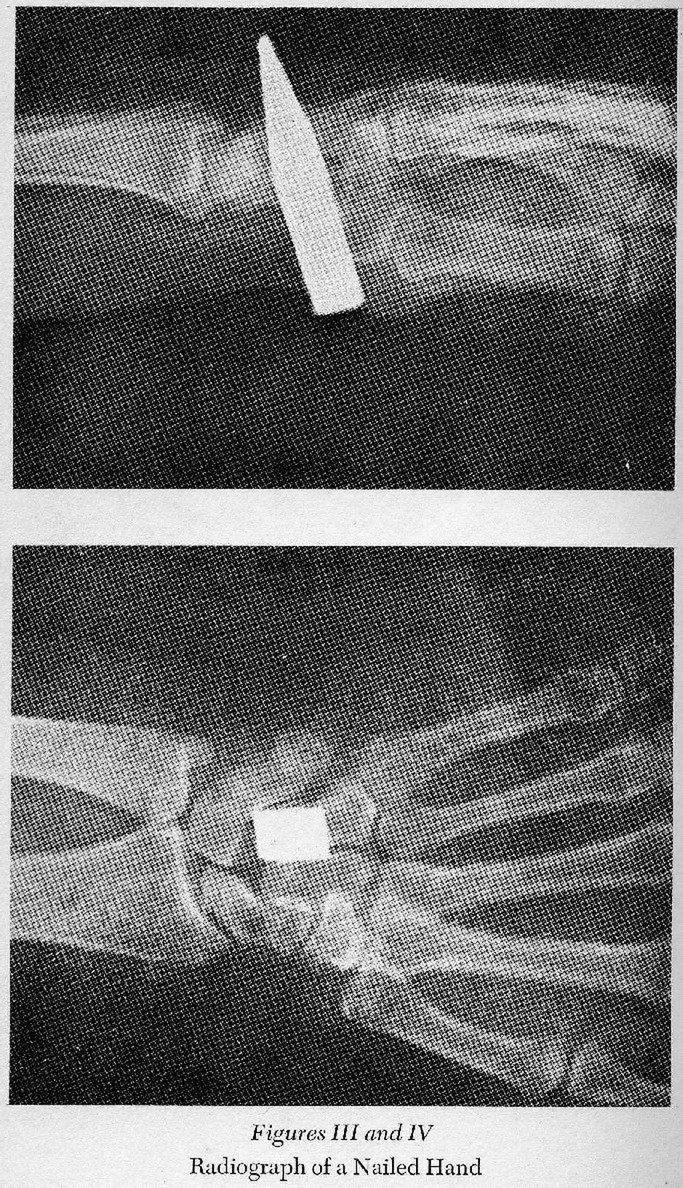

Na przedniej części wizerunku z Całunu łatwo można dostrzec ślady odbicia kończyn górnych. […] Wzdłuż obu przedramion widoczne sa długie nacieki krwi, które wychodzą z nadgarstków, dochodząc aż do wysokości łokcia” – piszą dalej Barberis i Boccaletti .

Już pod koniec XVI wieku wysunięto hipotezę, że miejscem przebicia gwoździa była nie dłoń, ale nadgarstek. Wiele lat później Barbet przeprowadził słynny eksperyment, który potwierdził te przypuszczenia:

„wziął amputowane ramię trupa i po wbiciu gwoździa w dłoń przymocował do niego (na wysokości łokcia) ciężar około 45 kilogramów […]. W przeciągu kilku minut zauważył, że ręka pod ciężarem się rozrywa i całe ramię razem z obciążnikiem spada na ziemię”.

11 / 20Święta tkanina czy falsyfikat? Cała prawda na temat Całunu turyńskiego

Obraz

© Materiały wydawcy

W 1968 roku podczas wykopalisk na wzgórzu Giv’at ha Mivtar odkryto groby żydowskie. Znaleziono tam szczątki około 30 osób, przy jednych widniało imię Jehohanan Ben Hgqwl. Był to prawdopodobnie jeden z buntowników skazanych na ukrzyżowanie: „kości prawej kończyny górnej miały otwory po gwoździu, między kością promienną a kością łokciową”, natomiast „w kość prawej pięty został wbity gwóźdź, przebijając obie pięty, a kości piszczelowa i strzałkowa po lewej stronie oraz strzałkowa po prawej były złamane”.

Wykazano później, że dokładnie taki sam proces krzyżowania był stosowany także w Judei na początku ery chrześcijańskiej.